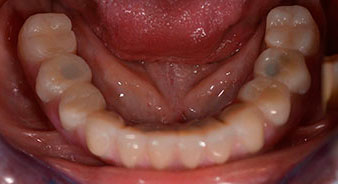

Following the time required for the osseointegration, the final impression of the implants could be performed and the final denture produced accordingly (Fig. 19 and 20). At this point, the dentist and patient were able to decide together whether to use a ceramic or acrylic veneer and a zirconium or metal framework. In this case, Dr. Pascu’s team decided on an acrylic veneer based on the unclear prognosis for the maxillary dentition and the fact that tooth 24 is elongated. This type of veneer is generally considerably easier to adapt and can thus be subsequently altered to reflect the new situation in the maxilla.

Osseointegration

Fig. 19

Implants

Fig. 20